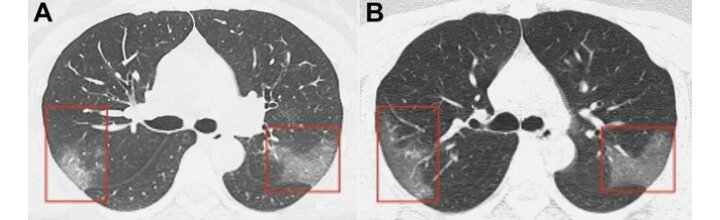

Так же появились снимки в сети с легкими заразившегося человека. На первом снимке видны помутнения, которые создают «эффект матового стекла». На втором, который был сделан три дня спустя, заметно, что пораженная область расширяется.